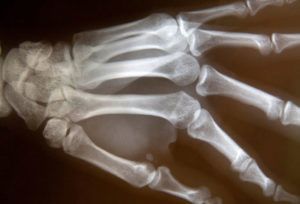

Болезнь называется — остеопения, что дословно означает “снижение количества костной ткани”. Кости меняют свою структуру и в них снижается количество остеоцитов. Строение скелета становится более пористым, что сказывается на устойчивости к ударам. Если остеопению не лечить, состояние становится более серьезным. Важно вовремя отреагировать на болезнь и не откладывать терапию на потом.

Болезнь сопровождается снижением плотности костной ткани, она теряет свой привычный минеральный состав и объем. Это происходит после того, как организм прекратил свой рост. Костные структуры стареют, что проявляется их хрупкостью и ломкостью.

Во время остеопении истончается поверхностный слой костей, так как в них снижается содержание фосфора и кальция. Это приводит к тому, что опасными для костей являются те ситуации, которые в норме не приводят к травмам — легкие удары, падения с небольшой высоты, подворачивания ноги.

Остеопению следует отличать от похожего состояния — остеопороза или остеомаляции. Эта болезнь наблюдается на фоне старения организма и болеют только те пациенты, которые достигли завершения развития костного скелета. К тому же, потеря минералов при остеопении не такая выраженная как при остеопорозе, который является закономерным последствием данного состояния.

Патология может затрагивать равномерно весь скелет или быть очаговой — в таком случае страдают некоторые кости. Если в скелете изначально было сниженное количество минералов — больше вероятность заболевания. Именно поэтому чаще болеют люди женского пола.